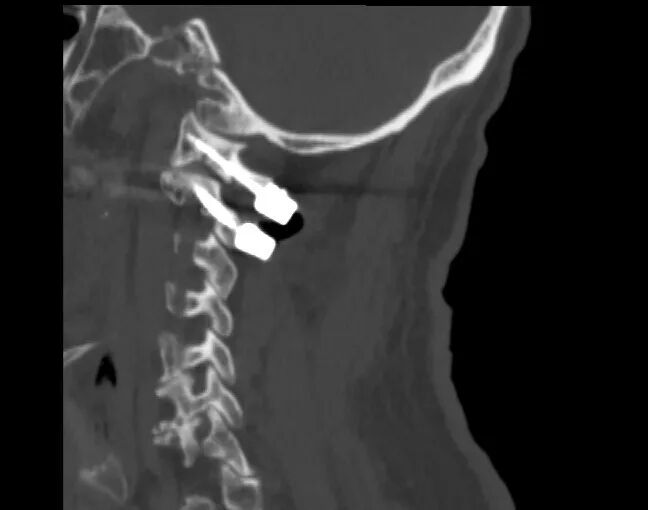

▲术后

手术全程顺利、创伤小、出血少,术后患者颈部疼痛明显缓解,肢体功能逐步改善,生命体征平稳,康复进展顺利。老人及家属连连致谢:“赶在春节前治好病,终于能过个安稳年了!